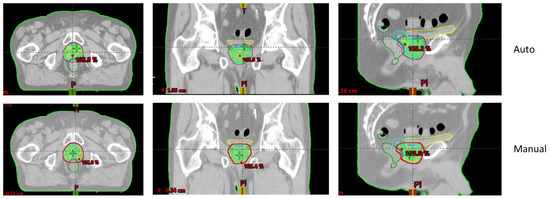

Figure 1 and Figure 2 show an example of dose distributions comparing automated and manual treatment plans for prostate-only localization. Another example for whole-pelvic irradiation is shown in Supplementary Materials Figures S1–S3.

Figure 2. Example of 40 Gy isodose for automated (upper—“Auto”) and manual (lower) treatment plans for prostate-only localization (Patient n° 7).